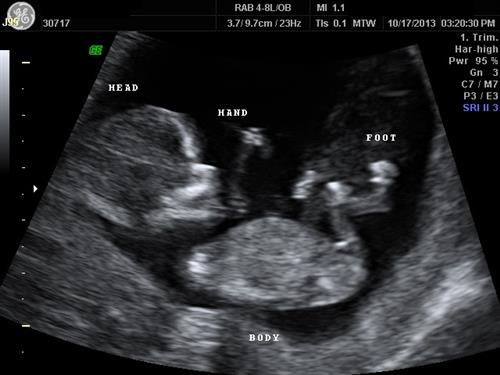

Click a thumbnail to view fullsize image.